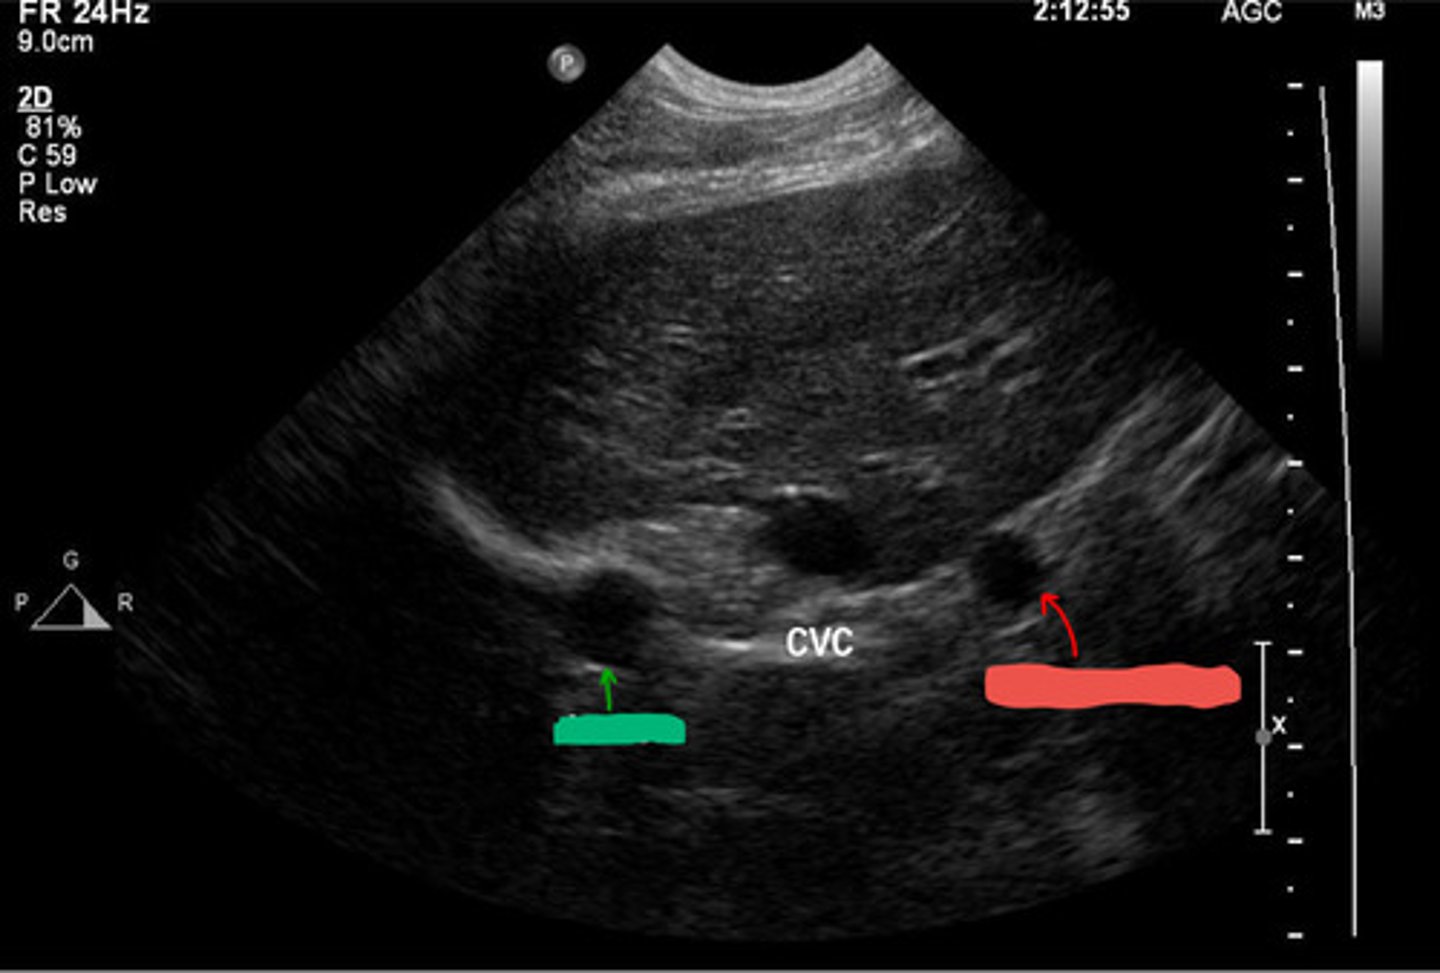

red- vena cava

blue- aorta

red- right side of body

blue- left side of body

orientation- transverse b/c round

ID red and blue, which one is on the right side of the body and which is on the left? what orientation is this?

vena cava

is the vena cava or aorta squishy?